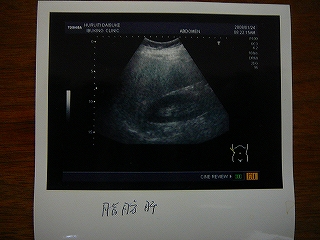

※けっこうエグイ画像(胃カメラ)がありますので 苦手な方はスルーしてくださいね~さてさて、24日に飲んできました、胃カメラ~前日の8時以降は夕食をとってはいけないのですが、こういう日に限って会議で遅くなり、家に着いたのが9時まあ、1時間ぐらいいいかと思ってたんですが、かあちゃんがご飯を片付けてました・・・ さすがにお腹空いたので、ユウマのおやつのハイチュウを1個だけ・・・それで次に日、24日の朝8時半頃に病院に行き、まずは超音波エコー、これは妊婦さんとまったく同じジェルをお腹にぬり、ぐりぐりと・・・横で見ていたことはありますが、自分がされるとなるとビミョ~な感触ですね・・・その後、すぐにメインの胃カメラへ・・・自分はとりあえず口からやったのですが、後で聞いたら鼻から入れる胃カメラも最近はあるみたいで、そちらのほうが”楽”みたいですね~まずは胃の中の泡を消す薬を飲み、胃の緊張をとる筋肉注射をしてそのあとは喉の麻酔薬?を喉元に5分間ほど溜め、これで準備終了です~なるべく力を抜いて、鼻で呼吸してください、と言われ胃カメラを挿入~モニターを見ていたんですが、胃カメラを動かされるたびに吐き気が・・・とてもモニターを見ていられる状態ではありませんでした~5分ぐらいで終了し、あとは検査結果待ち・・・まずはエコーの結果は・・・「脂肪肝」そして、胃カメラの結果は・・・「逆流性食道炎」これは胃酸が食道に逆流し、食道の粘膜を傷つけるらしいです・・・症状はご飯を食べてあとの胸焼け、ゲップ等~脂っこい食べ物を食べ過ぎたりするとなるそうです・・・そして最後に言われたのが「メタボリック症候群」なんかお医者さんに言われて「確定」ってカンジでカル~く落ち込みましたそりゃそうですよね、1年前の体重から約10kg増ですから・・・ ということで、やはり正月の目標に向かってがんばらないと・・・